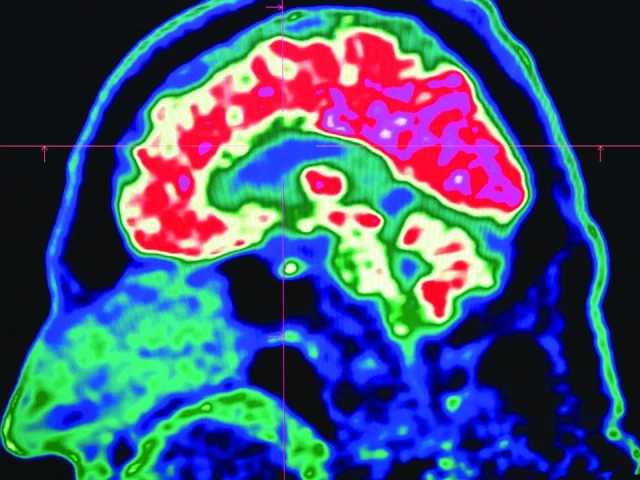

مانیٹرنگ ڈیسک (مشرق نامہ) چھوٹے چھوٹے پلاسٹک ذرات، جنہیں مائیکروپلاسٹک کہا جاتا ہے، اب انسانی دماغ میں بھی جمع ہوتے ہوئے پائے گئے ہیں۔ تاہم ماہرین کا کہنا ہے کہ فی الحال اس بات کے ٹھوس شواہد موجود نہیں کہ یہ ذرات انسانی دماغ کو نقصان پہنچا رہے ہیں۔

خبر رساں ادارے اے ایف پی کے مطابق یہ باریک ذرات دنیا کے ہر کونے میں پائے جا رہے ہیں — پہاڑوں کی چوٹیوں سے لے کر سمندر کی تہوں تک، ہماری سانس لینے والی ہوا، اور ہماری خوراک تک میں۔ یہ ذرات انسانی جسم کے مختلف حصوں میں بھی دریافت ہو چکے ہیں، جیسے پھیپھڑوں، دل، نالِ حمل (placenta)، اور اب دماغ میں بھی، یہاں تک کہ انہوں نے "بلڈ-برین بیریئر” (خون اور دماغ کے درمیان حفاظتی رکاوٹ) کو بھی عبور کر لیا ہے۔

مائیکروپلاسٹک کے دماغ پر اثرات سے متعلق سب سے اہم تحقیق فروری میں جریدے نیچر میڈیسن میں شائع ہوئی، جس میں امریکی ریاست نیو میکسیکو میں 2016 اور 2023 میں وفات پانے والے 52 افراد کے دماغی ٹشوز کا تجزیہ کیا گیا۔ اس تحقیق میں وقت کے ساتھ دماغ میں مائیکروپلاسٹک کی مقدار میں اضافہ دیکھا گیا۔

تحقیق کے سربراہ، زہریلی اثرات کے ماہر میتھیو کیمپن نے بتایا کہ وہ انسانی دماغ سے تقریباً 10 گرام پلاسٹک الگ کر سکتے تھے، جسے انہوں نے ایک نئے کریون (رنگ) سے تشبیہ دی۔